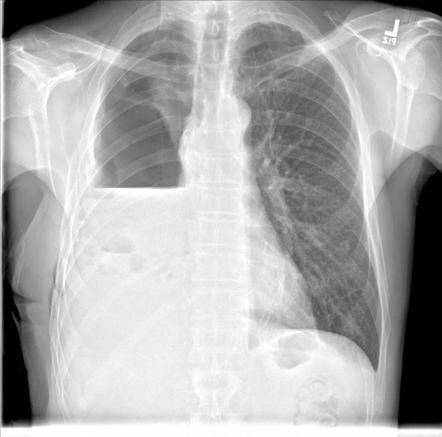

Investigations revealed:

A large amoebic liver abscess

Loculated pleural effusion

Communication of the abscess through the diaphragm into the pleural cavity

Involvement of the lower lobe of the lung, which had become diseased

Diagnosis: Hepatico-Broncho-Pleural Fistula secondary to ruptured amoebic liver abscess